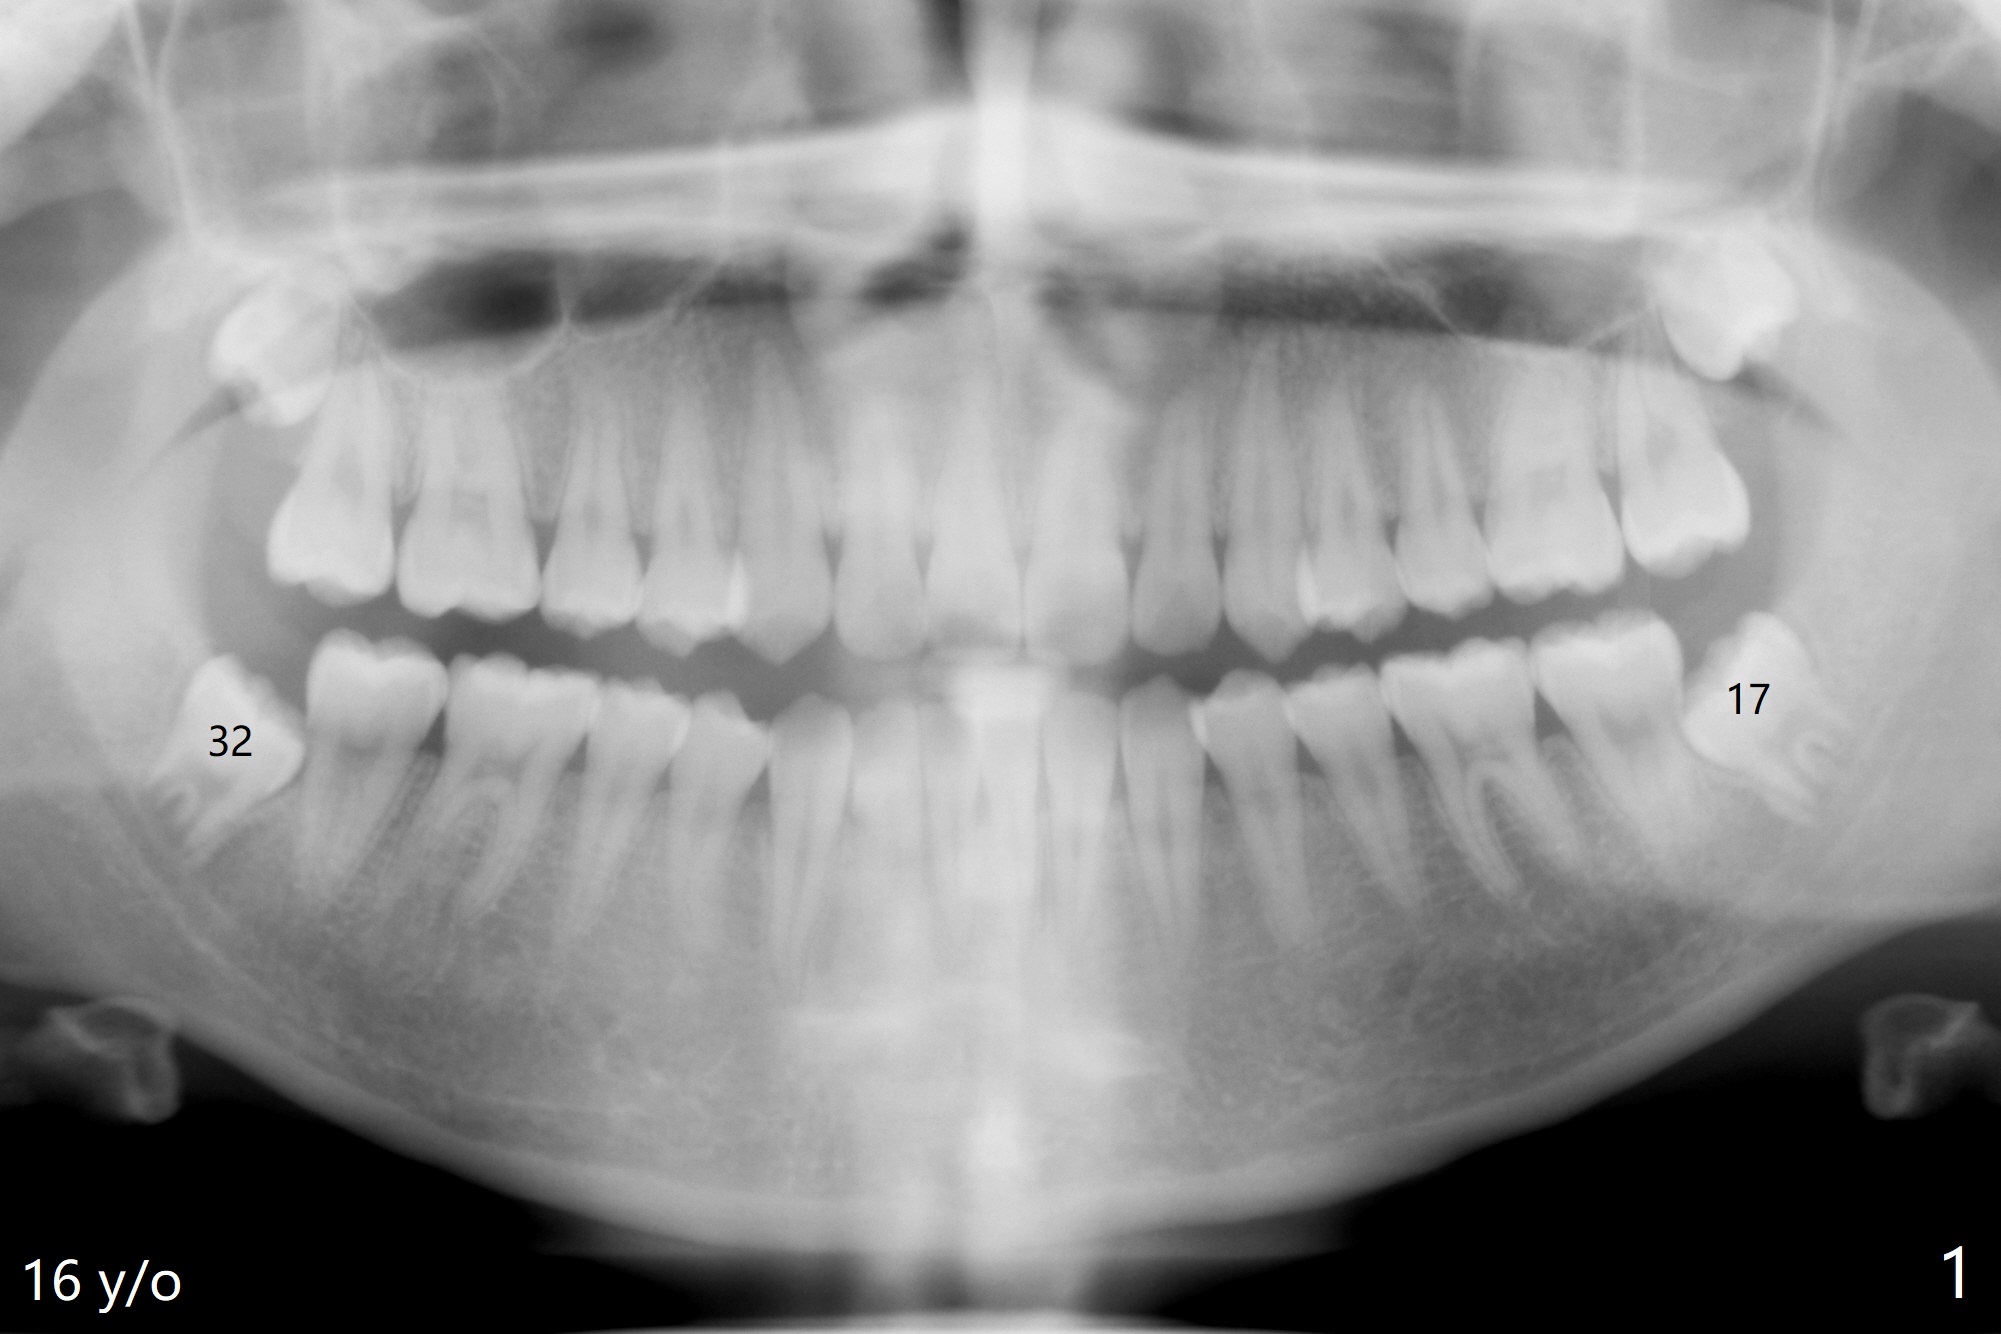

Sockets Post Osteogen Plug Placement

A 18-year-old woman has four of the 3rd molars extracted with placement of Osteogen Plug at #17 and 32 (Fig.1). Sockets seem to have healed 14 months postop (Fig.2,3).